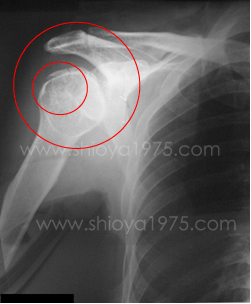

骨折や脱臼が疑われる場合は、状態を確認した上で応急処置として整復・固定を行います。

骨折・脱臼の応急処置と固定

骨折や脱臼は応急処置として整復し固定します

ケガの状態を評価し、患部に無理がかからないよう適切な処置を行います。